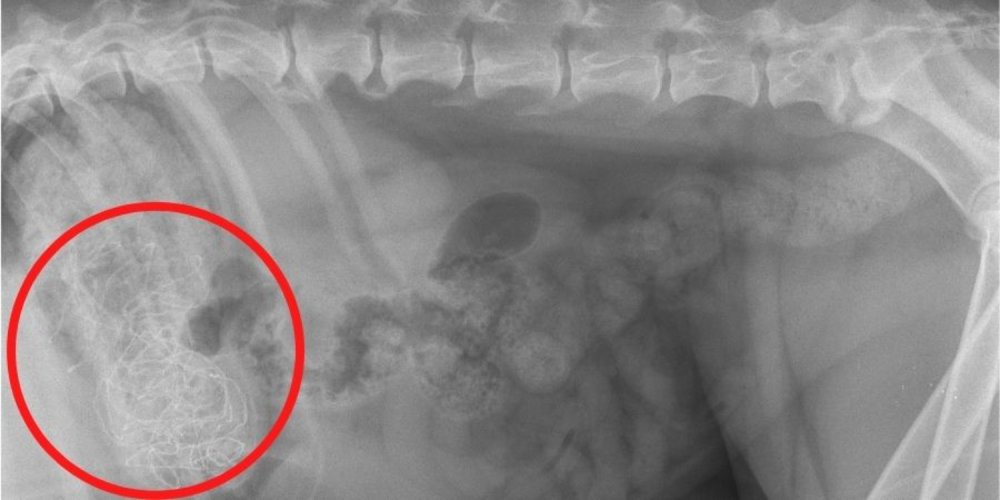

6. Igra Nintendo DS

Za Rocca je bilo igre skoraj konec, ko so veterinarji PDSA odkrili, da je radovedni pes pogoltnil igro Nintendo DS. Začel je bruhati in ni hotel jesti, zato so ga njegovi lastniki odpeljali v PDSA Glasgow Shamrock Street Pet Hospital na nujni pregled. Veterinarji so na rentgenskih slikah v njegovem črevesju našli pravokoten predmet in opravili nujno operacijo, da so ga takoj odstranili. Bili so osupli, ko so iz njegovega tankega črevesa izvlekli kartušo za video igro, a na srečo je Rocco preživel in je naslednji dan lahko odšel domov.